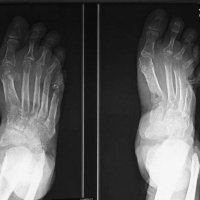

Osteomyelitis in diabetic foot is infection of the bone that 90% are results from contiguous spread of a skin ulcer. Consequently, the most common location for osteomyelitis is at the pressure points of the forefoot (metatarsal heads, IP joints) and in the hindfoot at the plantar aspect of the posterior calcaneus. Classic triad of osteomyelitis in plain radiograpy are lucencies, periosteal reaction, and bony destruction.

Unlike osteomyelitis, Charcot neuroarthropathy is primarily an articular disease and not related to overlying skin or soft tissue changes. Charcot neuroarthropathy commonly involves multiple midfoot bones. Features include joint instability, dislocation, destruction, disorganization, increased bone density, joint debris and deformity. Presence of subchondral cysts and intraarticular bodies with absence of the secondary signs for osteomyelitis support neuroarthropathy without infection.

In the early stage radiography will not demonstrate bone abnormalities, but MRI will show subchondral bone marrow edema. The subcutaneous soft tissues are not typically involved in Charcot arthropathy.

Osteomyelitis in chronic Charcot is usually located in the midfoot, while osteomyelitis in diabetic neuropathy without Charcot is usually in the forefoot and hindfoot.

Diabetic foot remains a challenge for the clinicians due to confusing clinical picture and associated complications. It may present as neuroarthropathy, septic arthritis, osteomyelitis, ischemic devitalised bone or as soft tissue complications such as cellulitis, myositis, ulceration, callus formation, sinus tracts, abscess, muscle denervation, tenosynovitis etc. Awareness of the various imaging findings of a diabetic foot, their relevance to the therapeutic decisions and correct usage of various imaging modalities to answer pertinent clinical questions are very important to improve the patient management and to reduce complications and morbidity.

Plain radiography is the preferred first line imaging investigation. It can show osseous structures and joint spaces well however it is neither sensitive nor specific. The detection rate and accuracy is low, especially in the scenario of early infection or neuroarthropathy, due to its lack of adequate demonstration of the soft tissues. In addition, Charcot’s foot and osteomyelitis may show overlapping radiographic features.